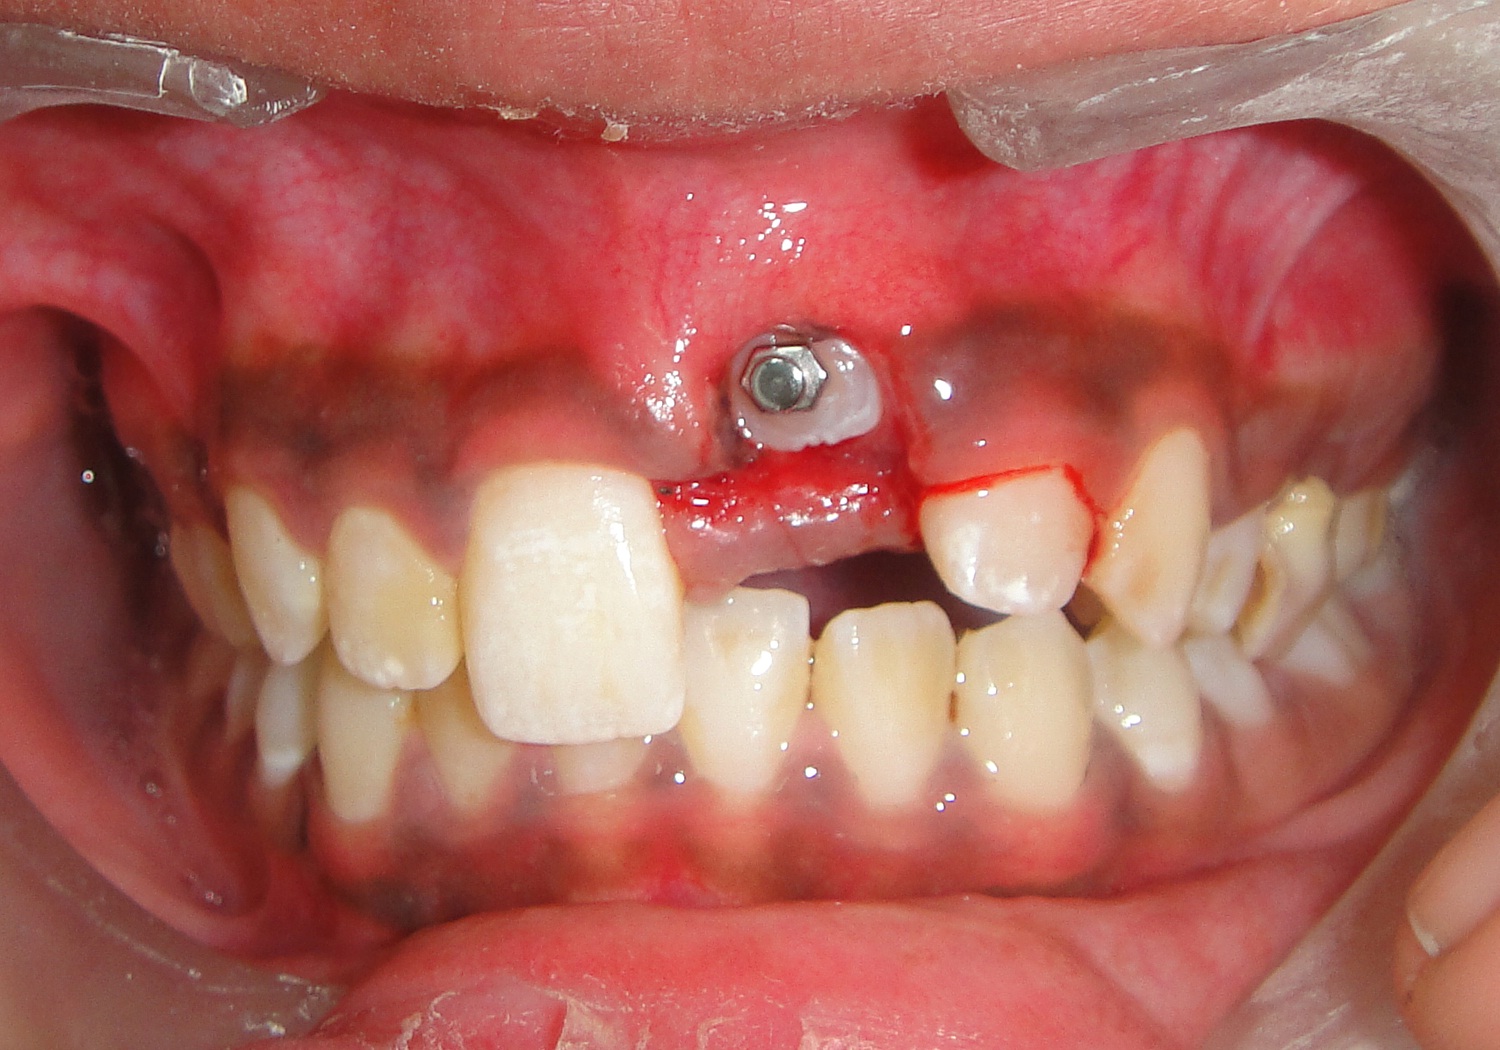

A 12-year-old female patient reported to the Department of Orthodontics of Maulana Azad Institute of Dental Sciences, New Delhi with chief complaint of missing upper front tooth. On clinical examination it was found that maxillary left central incisor (21) was missing [Table/Fig-1]. No significant history of trauma or premature/delayed shedding of primary left central incisor was reported. Panoramic and maxillary occlusal view revealed impacted left central incisor with dilacerated root [Table/Fig-2,3]. Since the contralateral central incisor had erupted fully in the mouth and the root formation of the impacted central incisor was almost complete, it was decided to disimpact the tooth (21). Disimpaction was planned by surgical exposure followed by elastic traction with the help of removable appliance. Since the patient had well aligned upper and lower arches in good occlusion, it was decided to use a modified removable appliance for extrusion of 21. A removable appliance with modified labial bow was fabricated. Labial bow in the anterior region was fabricated with 22 gauge wire and helices were incorporated in the labial bow adjacent to left central incisor region. Retention was provided by the acrylic coverage in the palatal region and by well formed retentive clasps. Surgical exposure of left central incisor was performed by open exposure technique. A bondable button was placed onto the labial surface of exposed left central incisor crown [Table/Fig-4]. Patient was trained to use elastic in triangular fashion to engage button on 21, and two helices of the labial bow, which resulted in an extrusive force of 20 grams for disimpaction of 21[Table/Fig-5] [1]. Patient was advised to change the elastic daily and was reviewed every three weeks. At the end of six months, complete disimpaction of 21 was achieved with the tooth in its optimal alignment into the upper dental arch and in good relation with lower teeth [Table/Fig-6,7]. Post disimpaction panoramic view reveals tooth 21 in the optimal position with respect to maxillary occlusal plane [Table/Fig-8].

Intraoral frontal photograph after surgical exposure and with bonded attachment on labial surface of 21.